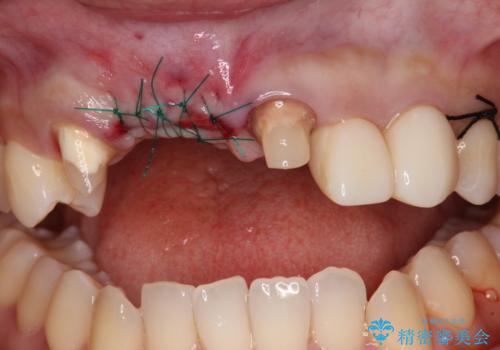

- 前歯を2本抜歯した後に装着した仮歯が長く見えるのが気になるとのことで来院された患者様です。

抜歯後には歯を支えていた骨が失われるため、歯肉が痩せてしまい、結果としてブリッジのダミーの歯を長くする必要があります。

前医では、歯肉の位置に相当する部分を、歯肉に近い色とすることで歯の長さが揃っているようにカムフラージュする治療が提案され、仮歯もそのようになっていました。

歯肉が痩せてしまっている状態を改善するため、口蓋から歯肉の結合組織を採取し、移植することで厚みを増大させることとし、その後オールセラミックブリッジにて補綴治療を行うこととしました。

1回の歯肉移植により歯肉の厚みは大幅に改善されましたが、折角なのでもう少し大きくしたいとの要望があり、2回目の処置も行うこととしました。